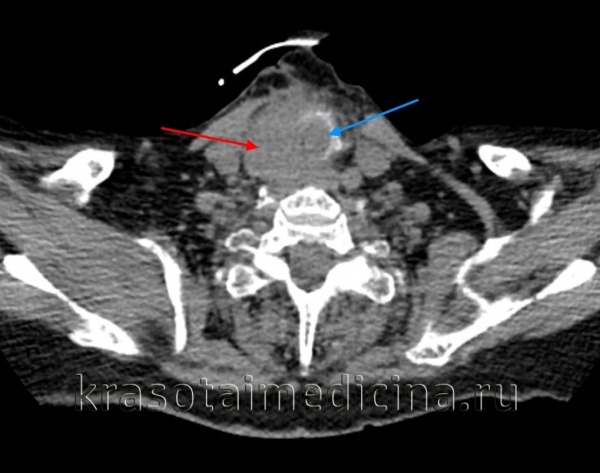

КТ шеи. Инвазивная опухоль щитовидной железы (красная стрелка) с прорастанием в трахею (синяя стрелка).